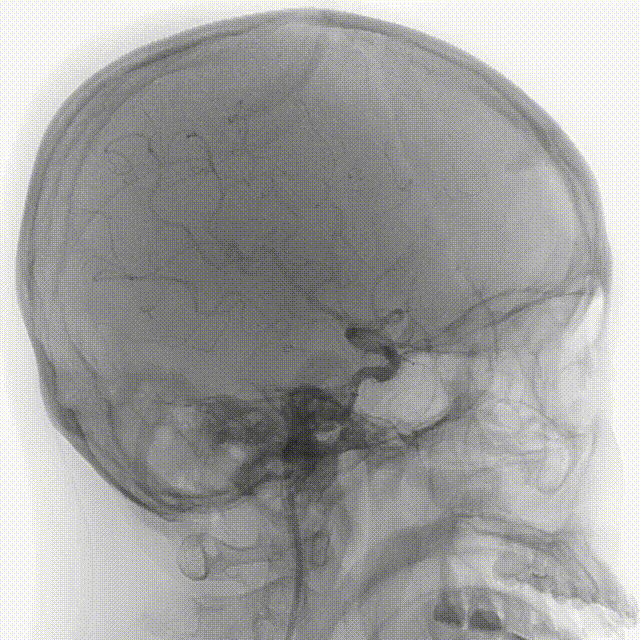

右侧颈内正位造影

右侧颈内侧位造影

载瘤动脉远端血管直径:2.1mm

载瘤动脉近端血管直径:1.8mm

动脉瘤尺寸:瘤颈4.69mm,大小3.25mm*4.21mm*4.24mm;指向右上

近端狭窄:最窄处:0.53mm,远心端2.1mm,近心端2.2mm,长度11.23mm